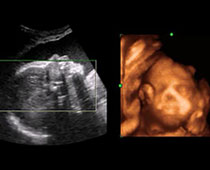

- Fetal Face Ultrasound Photos

- 3D Fetal Profile Ultrasound Scan Photos

- The Clinical Advantages of 3D and 4D Ultrasound

- Definition and Features of Four Dimensional Ultrasound

- Uses of 4D Ultrasound scan

- Fetal behavior during pregnancy